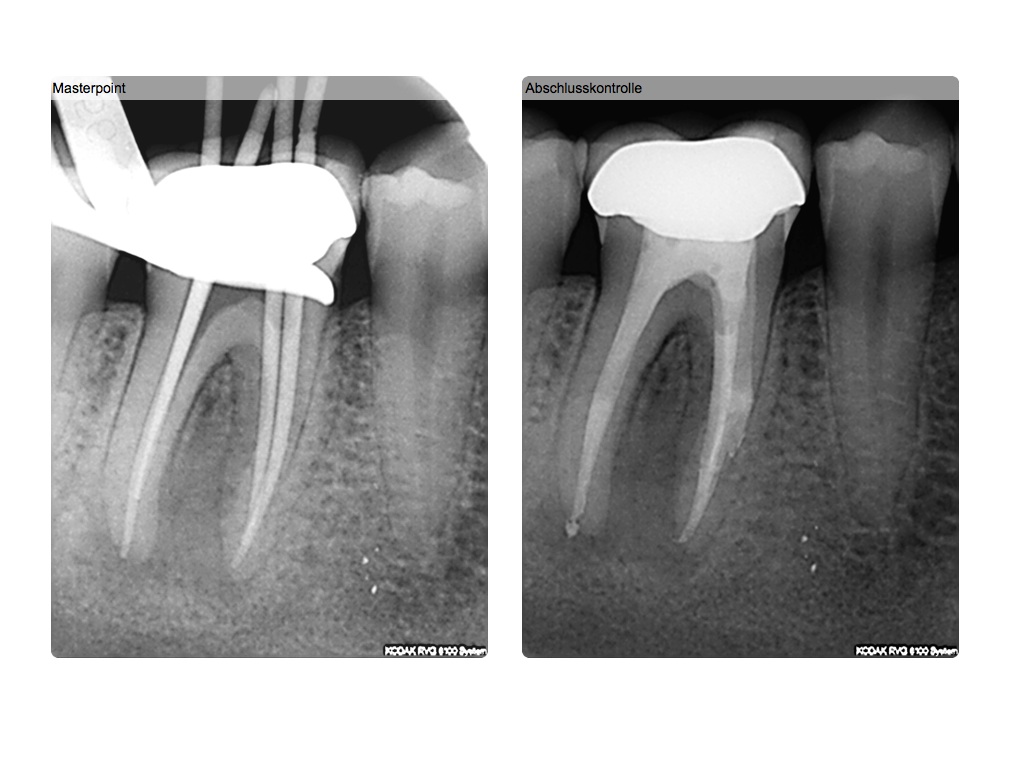

Röntgenbilder lügen…